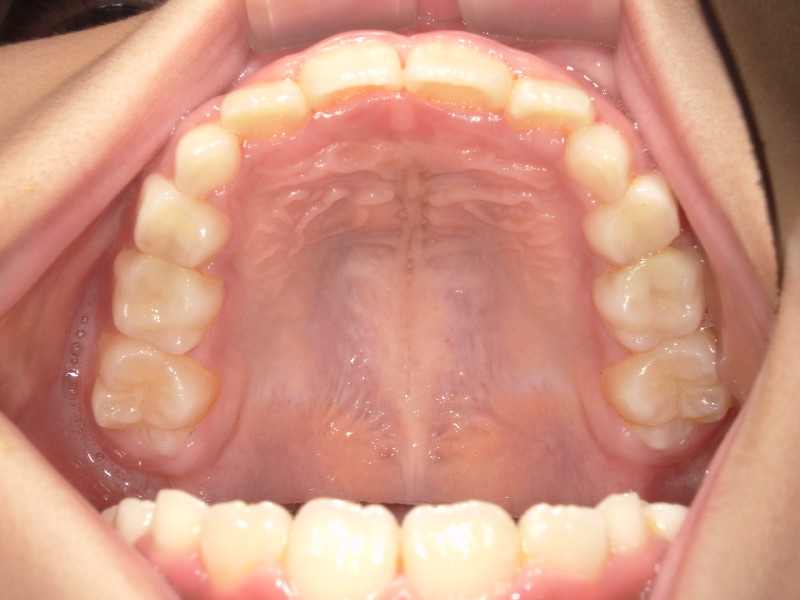

一年の上の顎の変化です。

写真左側の前から2番目の歯は大きく、今の顎のアーチの中に入れないため後ろから出ています。

右側はまだ乳歯ですが横にぴったりなので生え変わる時が経つくことが予想されていました。

ですがマウスピースとアクティビティーを進めることでしっかりと前歯の4本が横に並んでいます。